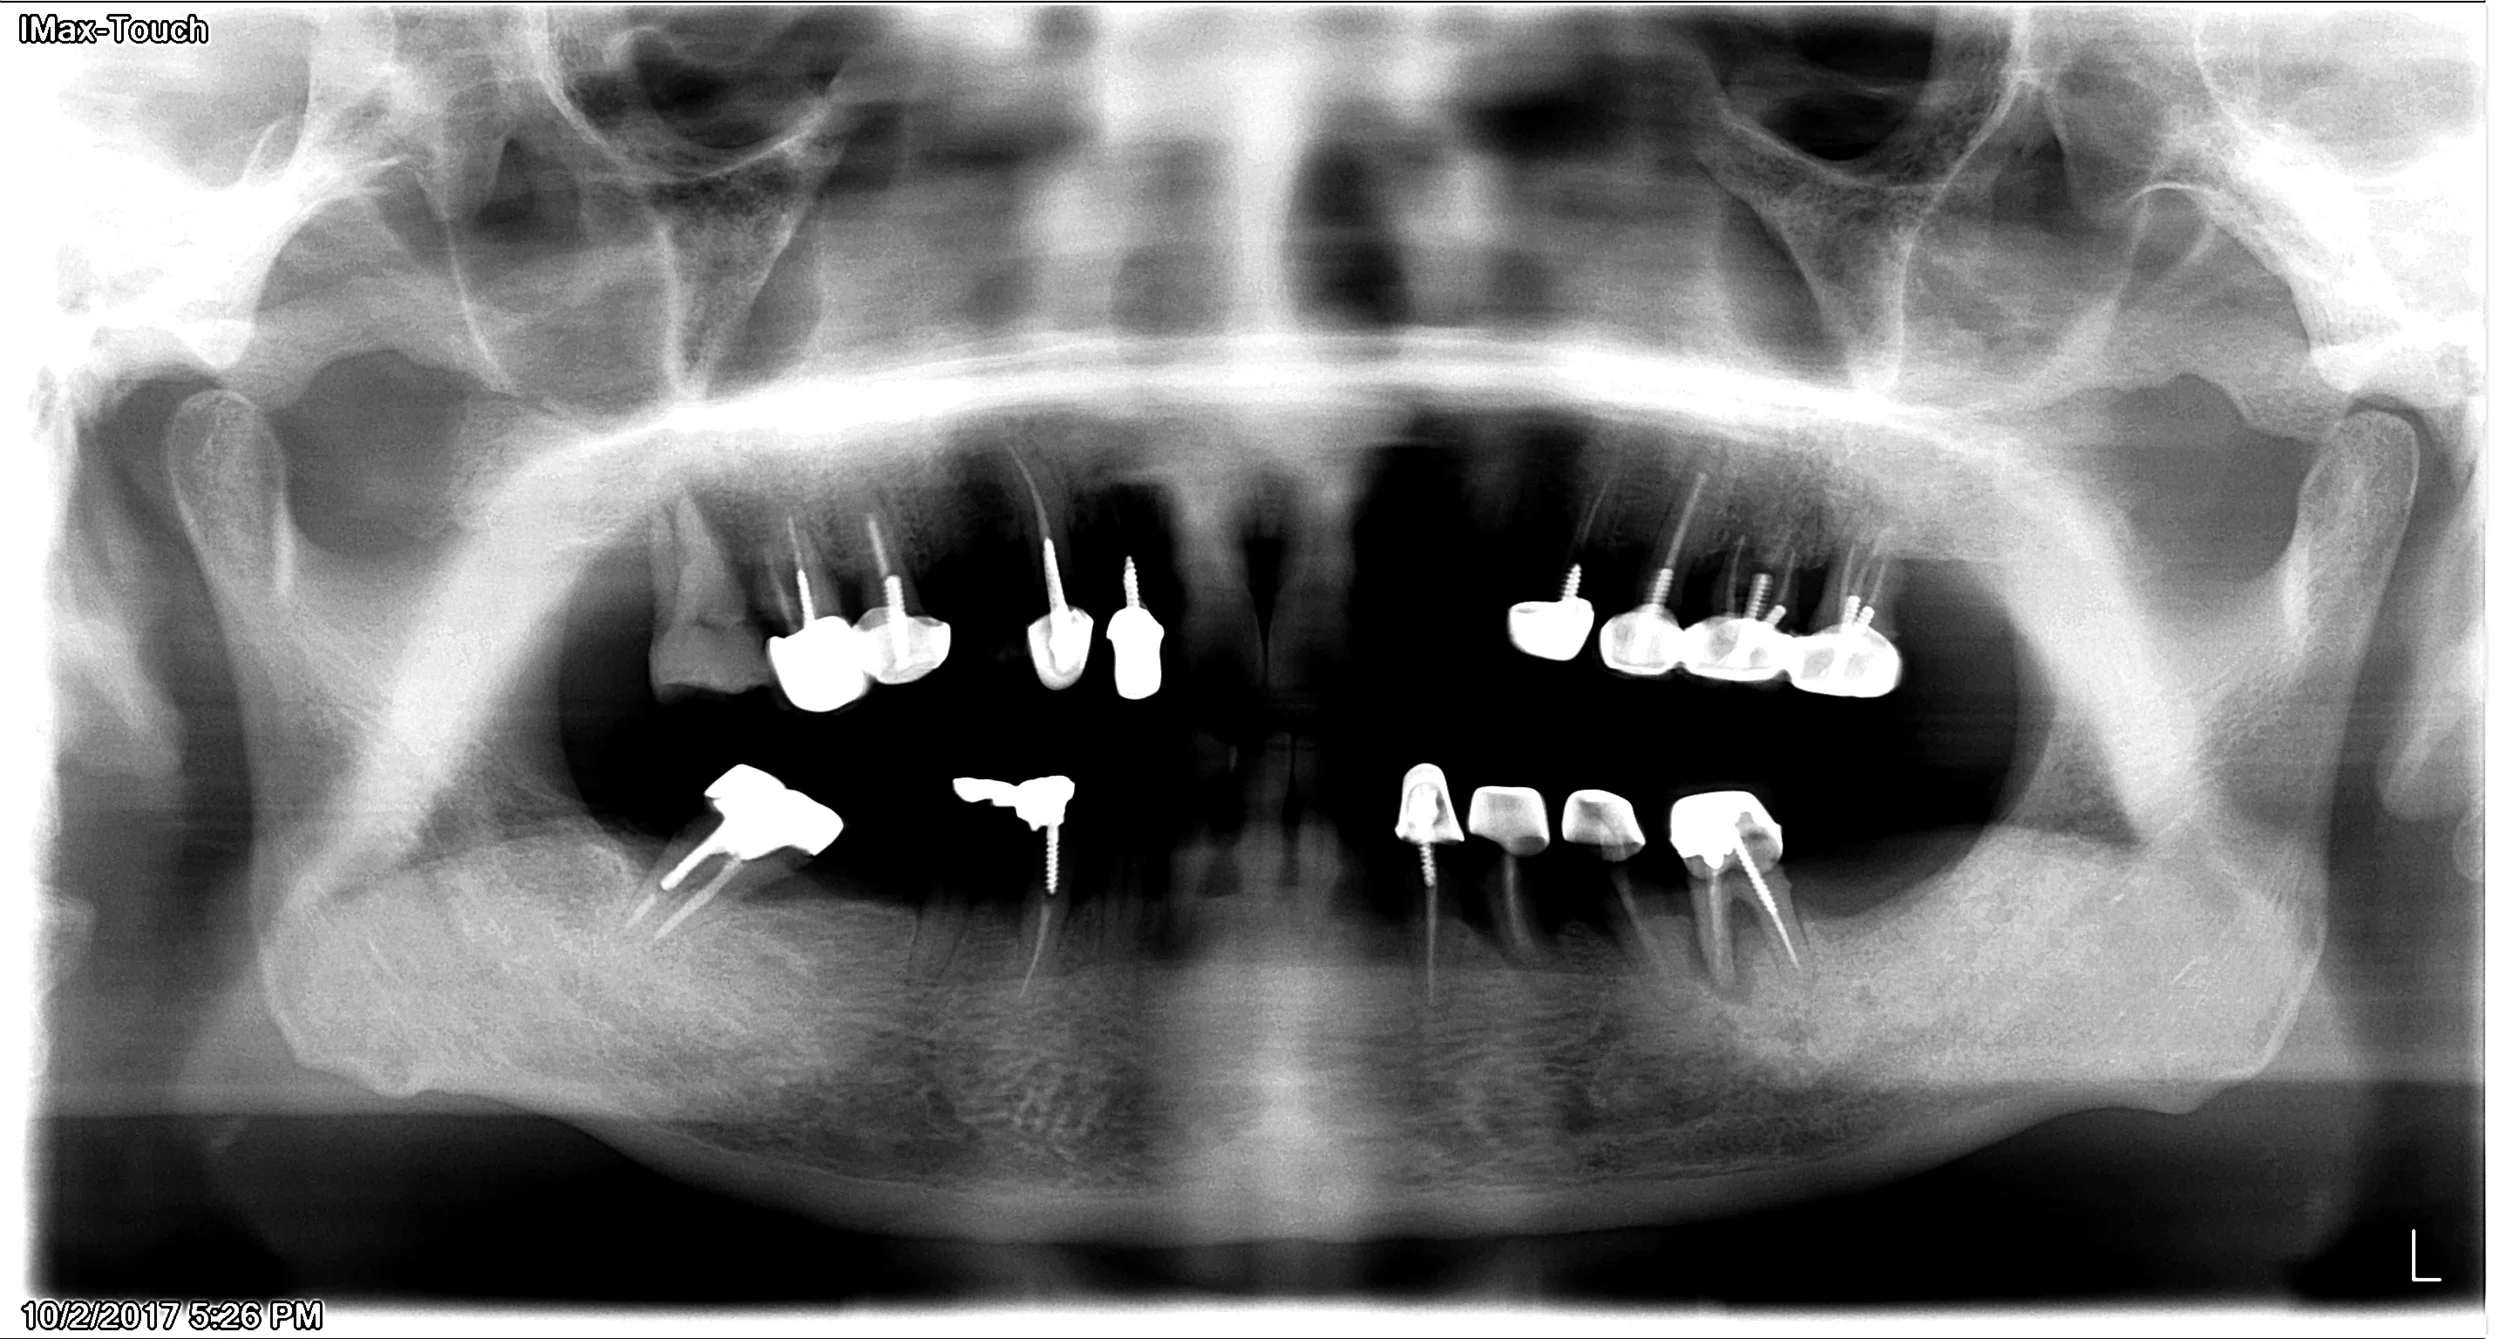

Case #4: This 60 year old male patient came in with severe periodontal disease. Note that he already had dental implants done in another office 1 year ago. You can see the dental implants on lower right side is getting bone loss.This 60 year old male patient came in with severe periodontal disease. Note that he already had dental implants done in another office 1 year ago. You can see the dental implants on lower right side is getting bone loss.

All upper implants has been placed in our office. Note that lower right implant (done in another office) continues to have bone loss. They will eventually fall out and would require extensive bone grafting. Patient are able to get more dental implants on lower right side if he's lucky and bone loss is not extenisve. If bone loss is extensive on failing implant, patient might not have enough bone for further dental implants in that area. This is an example it is very important to find a good, experienced and skilled clinician to do these procedures because sometimes you really only have 'one chance'.

Upper implant in temporary phase.

Note the amount of bone loss on the lower right implants that was done by another office. There can be many reasons that can lead to this type of failure, it takes an experienced clinician to avoid these type of issues. These failing implant would need to be removed and bone grafted, hopefully, new dental implants can be placed.